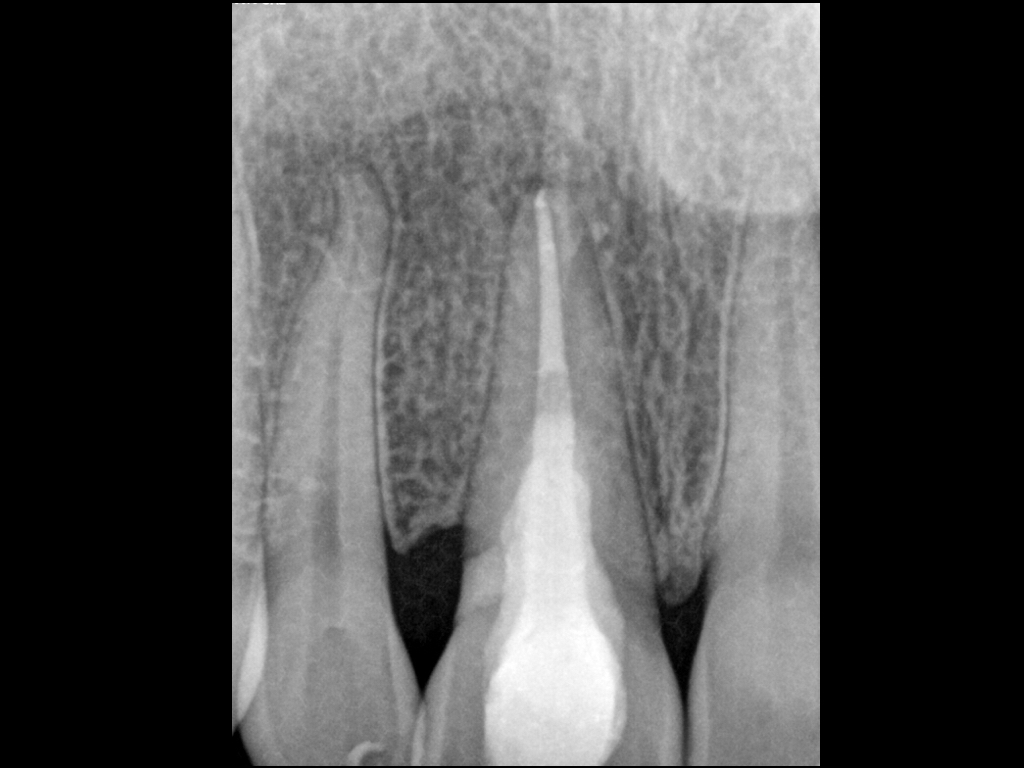

wsi-112016-2-013

Herodontics (1)